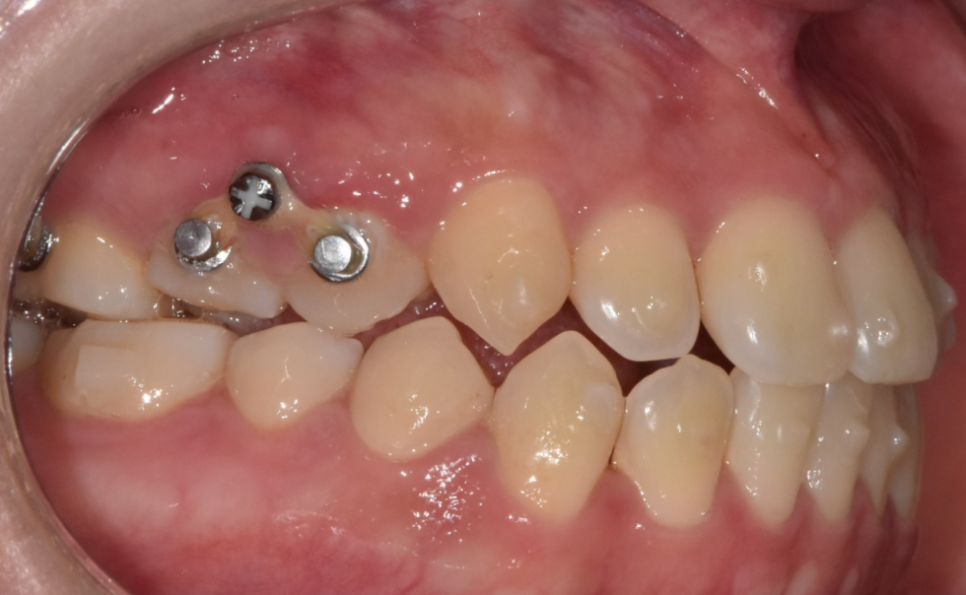

교정치료는 치아가 이동하는 방향과 힘의 조절이 매우 중요합니다.

치아 뿌리 쪽에 스크류가 식립되는데

돌출입 , 덧니 교정 , 부정교합 여러 케이스에 활용됩니다.

특정 치아를 움직여야할 때

발치 후 공간 폐쇄

큰 치아 이동이 필요하여 추가적인 힘이 필요할 때

정말 다양한 경우에 활용되고 있습니다!